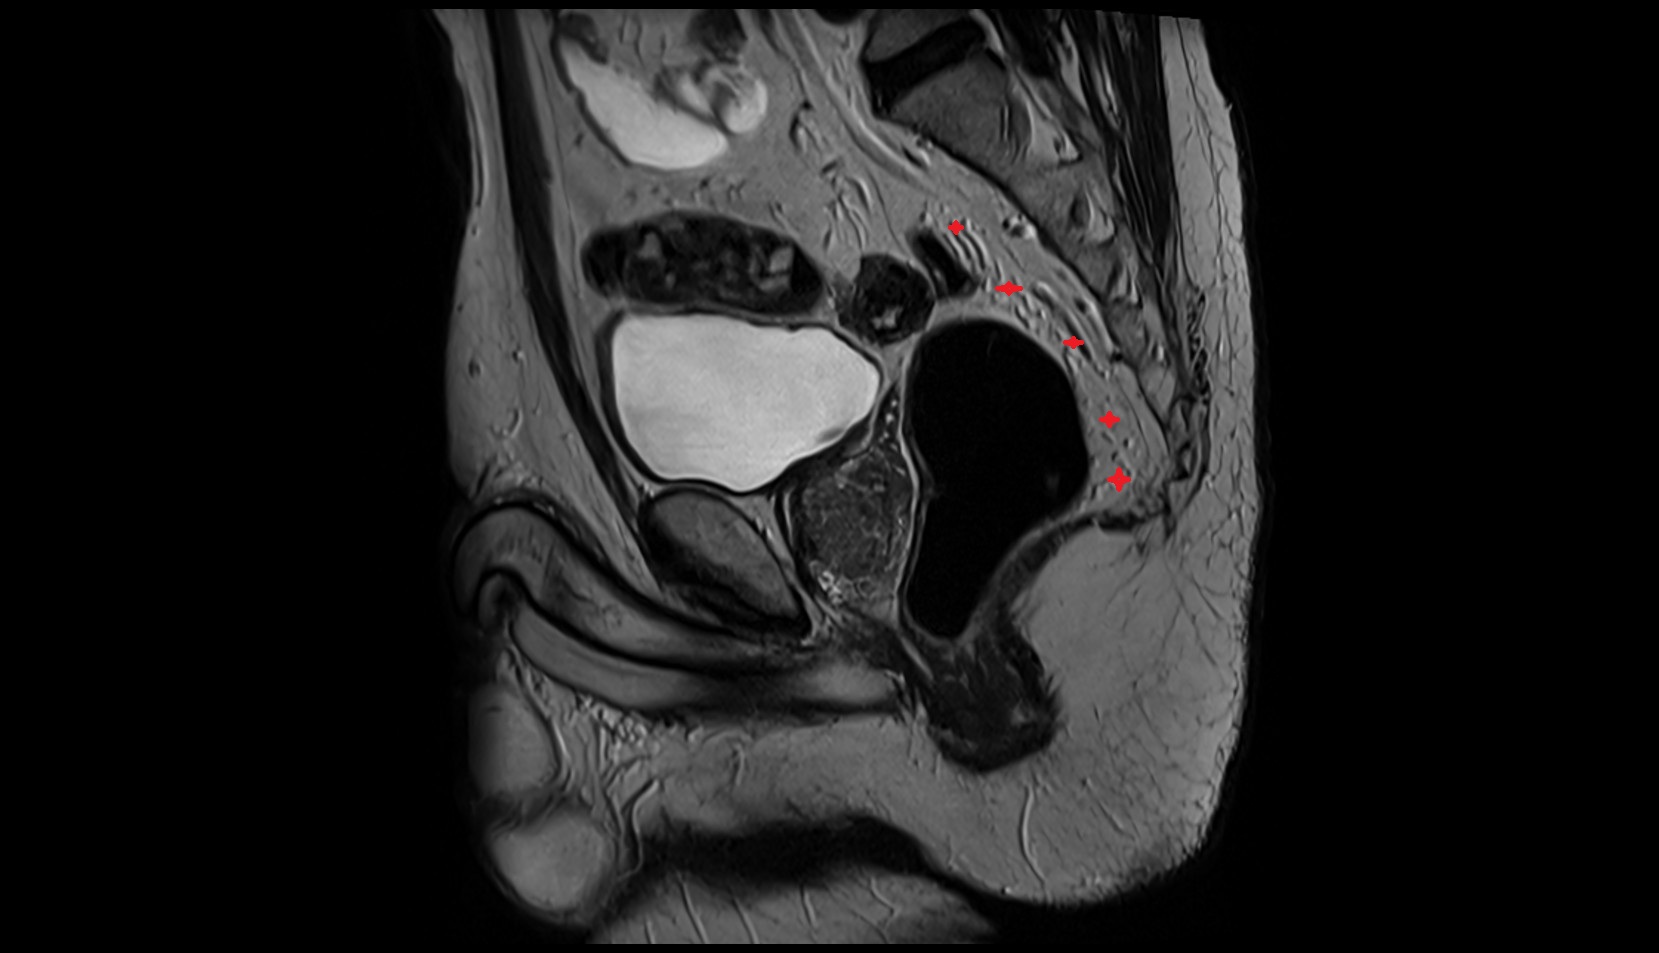

- Membranous urethra

- Prostatic urethra

- Penile urethra

- Rectoprostatic fascia (Denonvilliers' fascia)

- Rectosacral fascia (Waldeyer's fascia)